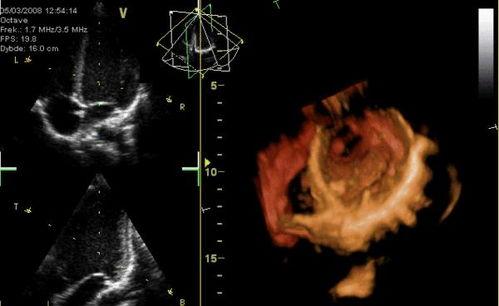

你知道吗,心脏跳动其实是一种非常复杂的生理现象。它是由心脏的肌肉组织自动收缩和舒张产生的。而心脏跳动视频,就是通过高科技手段捕捉到的心脏跳动画面。这些视频通常是通过医学影像技术,如超声心动图、心电图等设备拍摄而成的。

心脏跳动视频不仅能够展示心脏的跳动过程,还能让我们直观地看到心脏的结构和功能。比如,通过心脏跳动视频,我们可以看到心脏瓣膜的开关、心室的收缩与舒张等。这些信息对于心脏疾病的诊断和治疗具有重要意义。